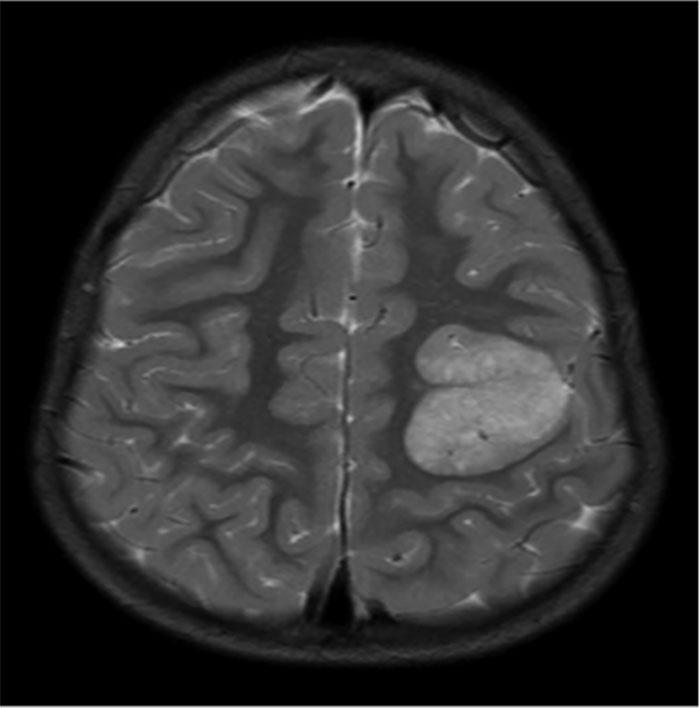

Back in 1990 was completing a group autopsy in an advanced human anatomy class. 85 year old patient had a tumor in her brain. It was the size of a Golfball on her right lobe. Unknown to her prior to death, her physician. Died in her sleep naturally. The tumor was not malignant but most likely caused some wicked headaches along with other symptoms. The stuff you find. The body is a wonder.